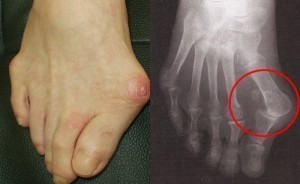

注意!外反母趾は悪化すると脱臼します

最近 親指が脱臼しているのに自分では気がついていない外反母趾の方が、私から指摘を受けてビックリされるケースが多くみられるようになりました。

脱臼と聞くと格闘技の関節技で「バキッ」と無理に外されてとても痛いもの・・・というようなイメージをお持ちではないでしょうか?

外反母趾の脱臼は普通の怪我のような急性のものとは違い、変形が徐々に進行し親指が関節から少しずつ外れていく過程をたどります。

そのため脱臼の痛み自体はほとんど感じられない、本人は親指の曲がりが進行した程度の認識しかなく、まさか自分の親指が脱臼してるとは思ってもいません。

以前は親指の脱臼を伴う外反母趾は、60~70代の年齢を中心にみられていましたが、最近は40代ですでに脱臼している方もみられようになってきました。

一般の方は多くの外反母趾の症例を目のあたりにする機会がありませんので、外反母趾が悪化すると脱臼してしまう事実をほとんど認識されていません。